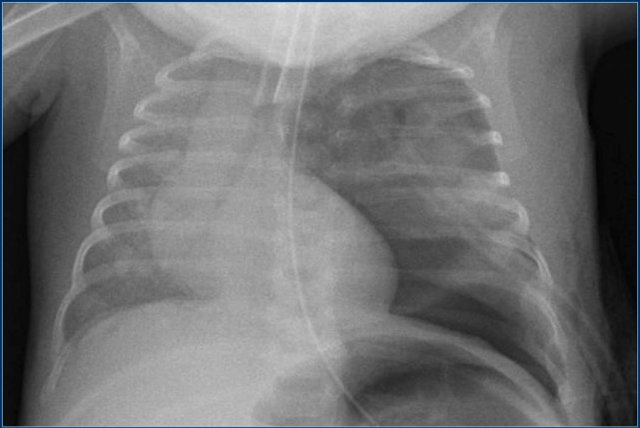

Umbilical artery line (5)

First study the images.

Then continue reading.

The findings are:

1. Malposition of umbilical artery line in left iliac artery.

2. Deep position of umbilical vein line in right atrium.

3. Good position of gastric tube.